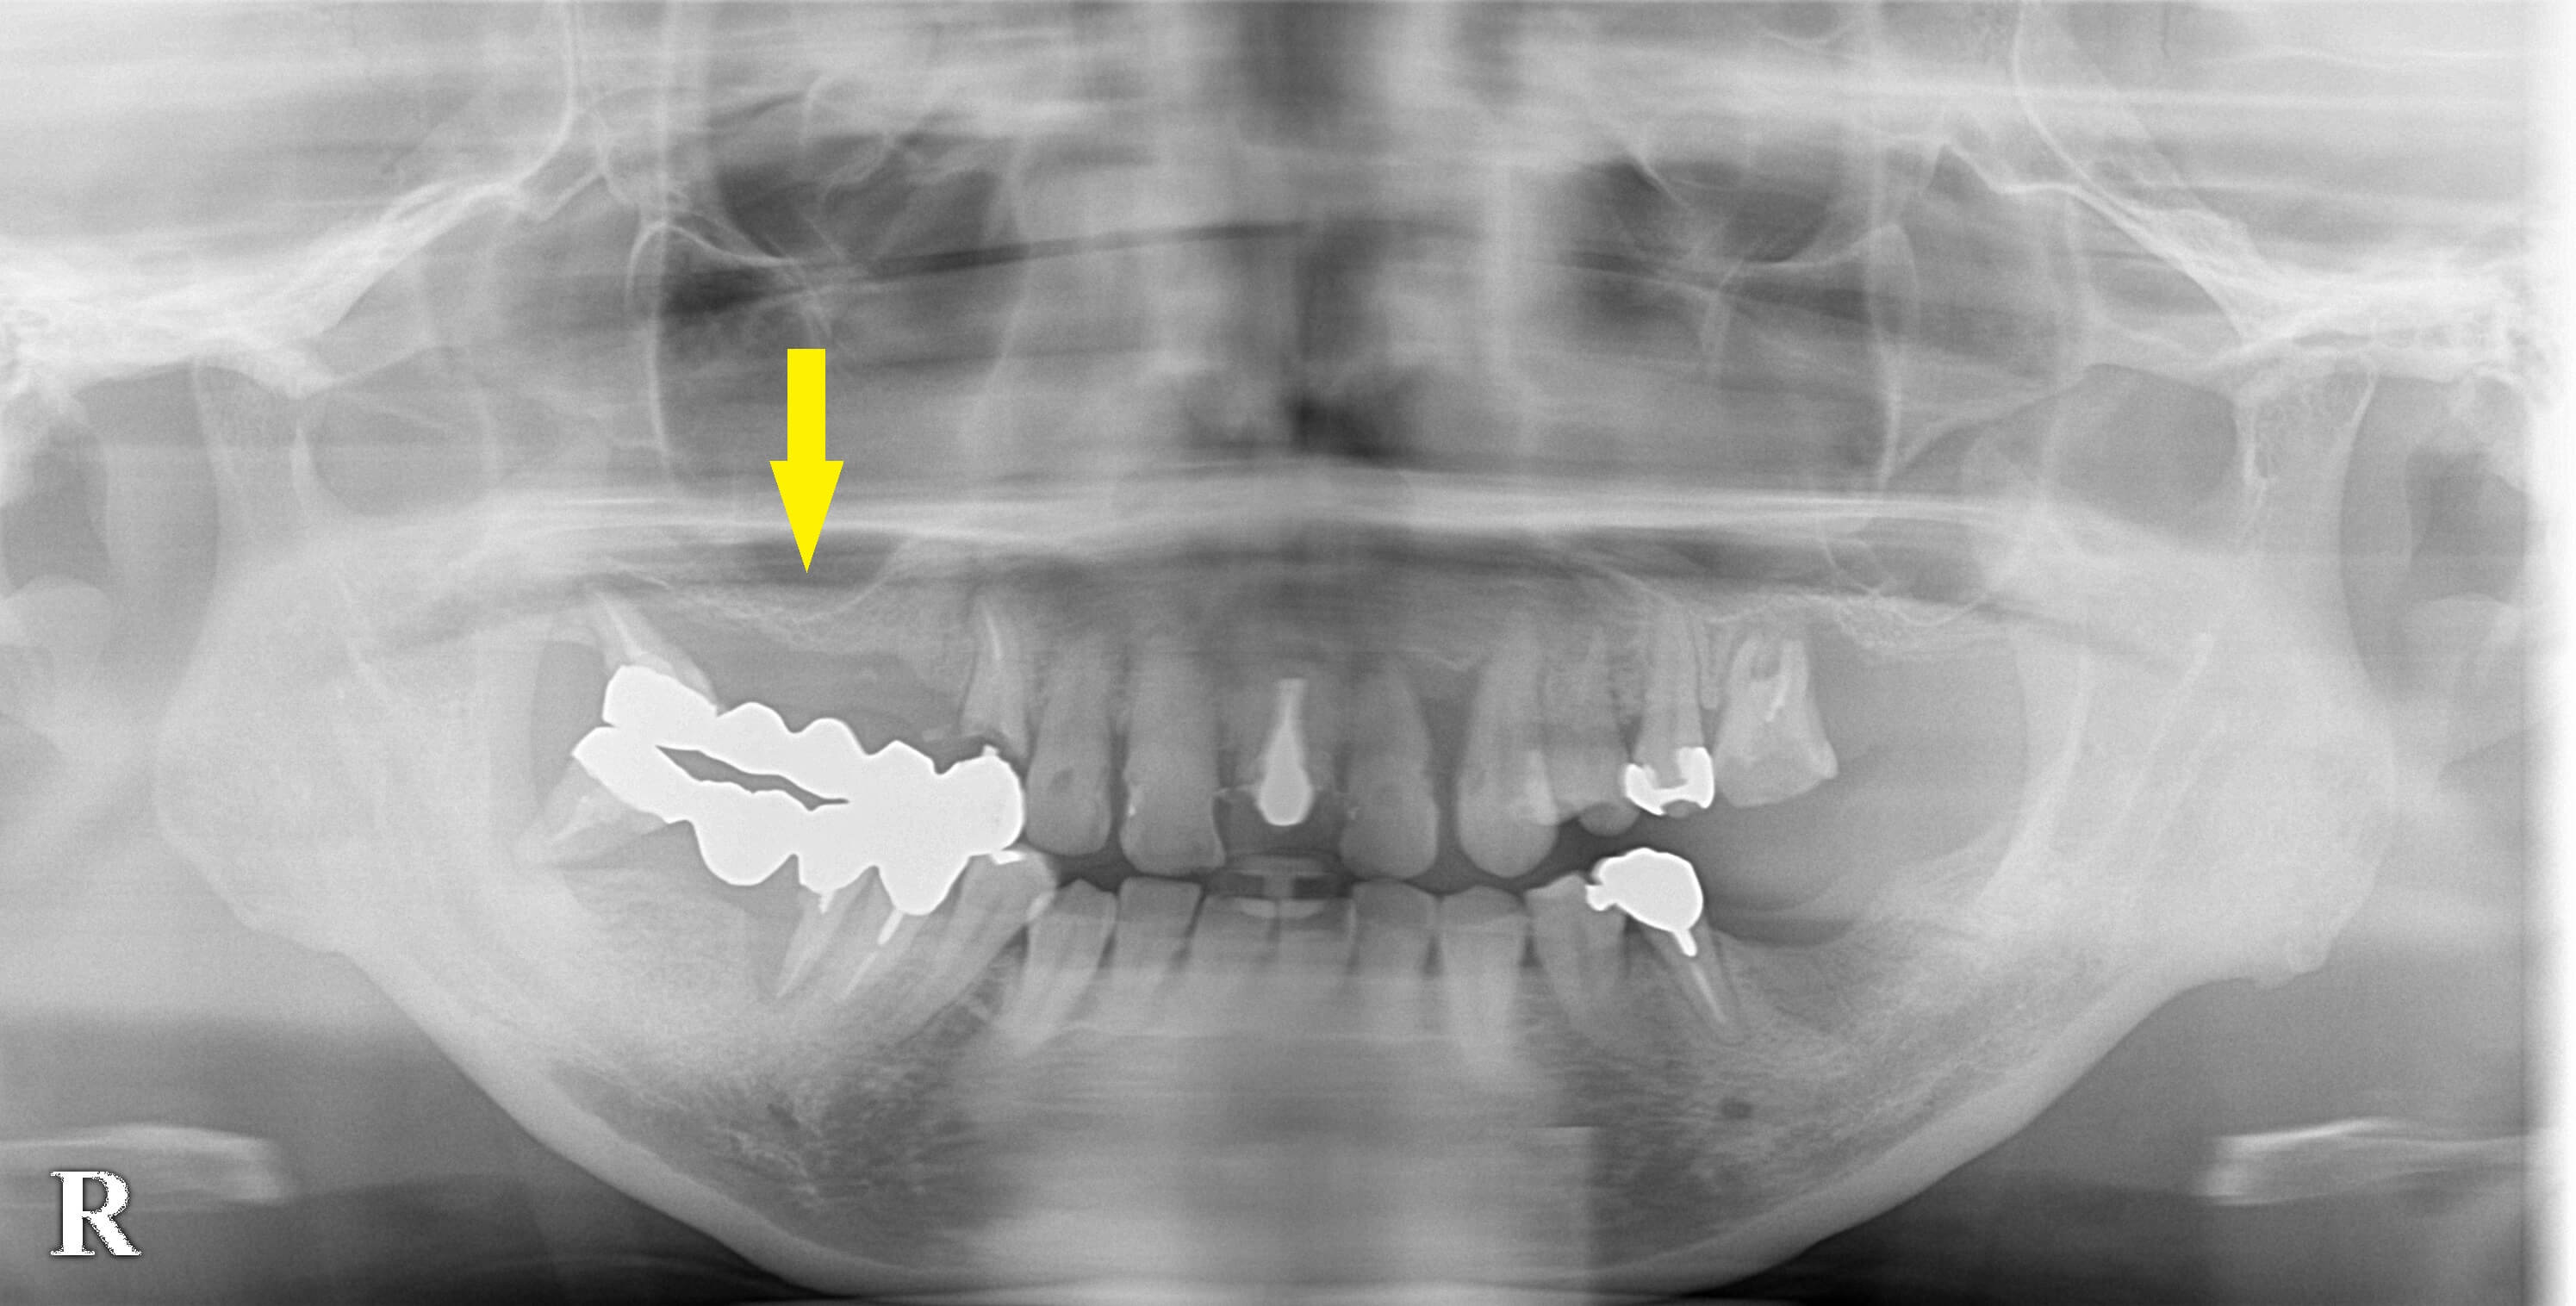

右上顎のブリッジがグラグラになり、同部のインプラント治療を希望されて相談にお出でになりました。

犬歯から後方に長いブリッジが装着されていたのですがほぼ外れてしまった状態でした。

下の写真上段が術前のレントゲン写真、2段目が術前のCT、3段目がサイナスリフト後、4段目がインプラント埋入後のCTです。